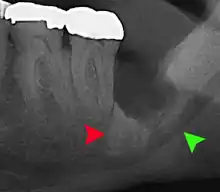

Coronectomy

Coronectomy is a procedure where the crown of the impacted wisdom tooth is removed, but the roots are intentionally left in place. It is indicated when there is no disease of the dental pulp or infection around the crown of the tooth, and there is a high risk of inferior alveolar nerve injury.[32]

Coronectomy, while lessening the immediate risk to the inferior alveolar nerve function has its own complication rates and can result in repeated surgeries. Between 2.3% and 38.3% of roots loosen during the procedure and need to be removed and up to 4.9% of cases require reoperation due to persistent pain, root exposure or persistent infection. The roots have also been reported to migrate in 13.2% to 85.9% of cases.[32]